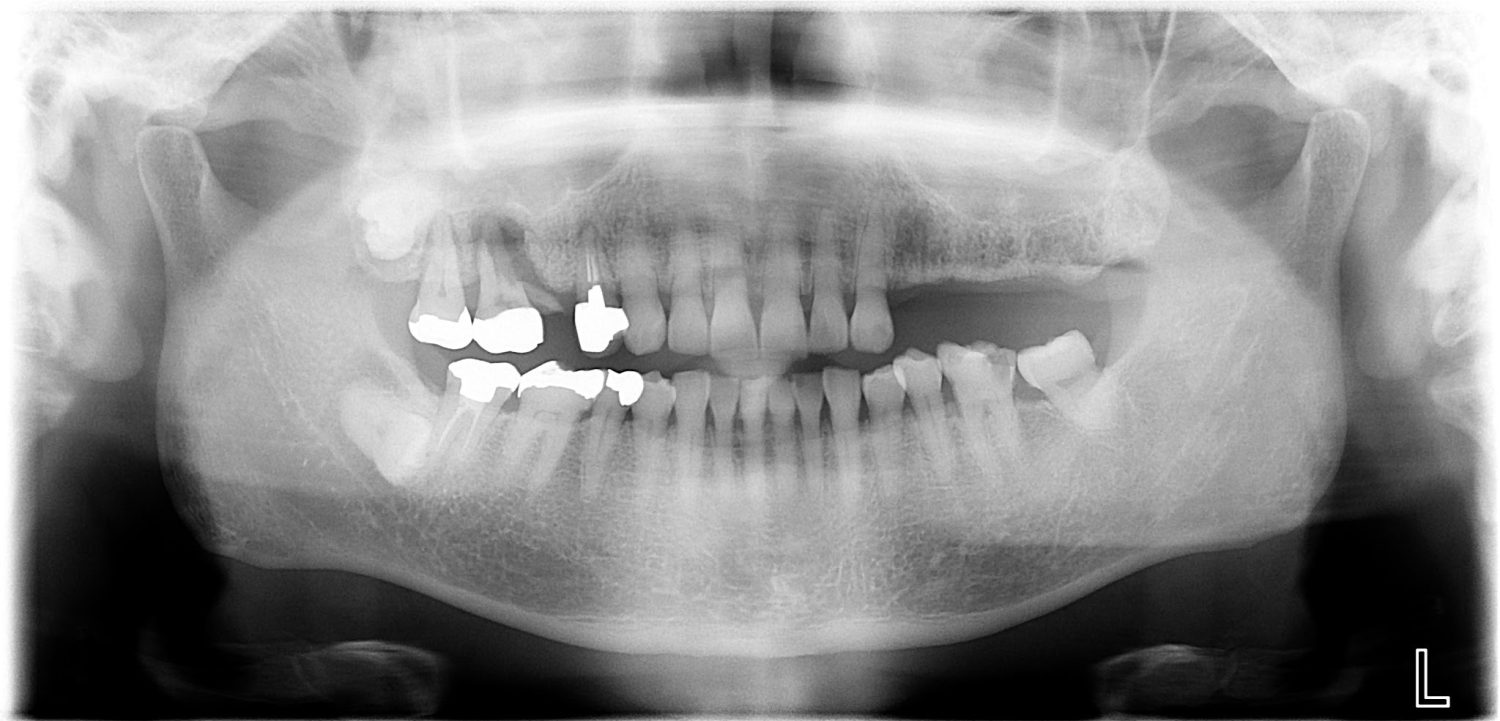

インプラント治療の症例紹介③

Before

After

主訴

むし歯の治療

治療内容

保存不可能な歯の抜歯

下顎にインプラント埋入し咬合再構成

治療費

2,688,400円(税込)

治療期間

14か月

治療回数

21回

想定されたリスク

※上部構造の形態が複雑になるため清掃が難しくなる。インプラント周囲炎の恐れがありました。

多数歯う蝕および多数歯欠損による咬合崩壊、保存不可能な歯の抜歯により上下無歯顎に。下顎に6本インプラント埋入する事で咬合再構成を行った。